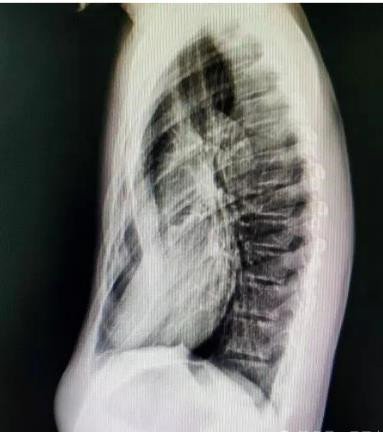

若发现孩子胸口有凹陷,及时带娃到胸外科就诊,通过胸部 X 线、CT 扫描、肺功能测试、心脏超声等检查,明确凹陷程度和心肺受压情况,避免延误干预时机。